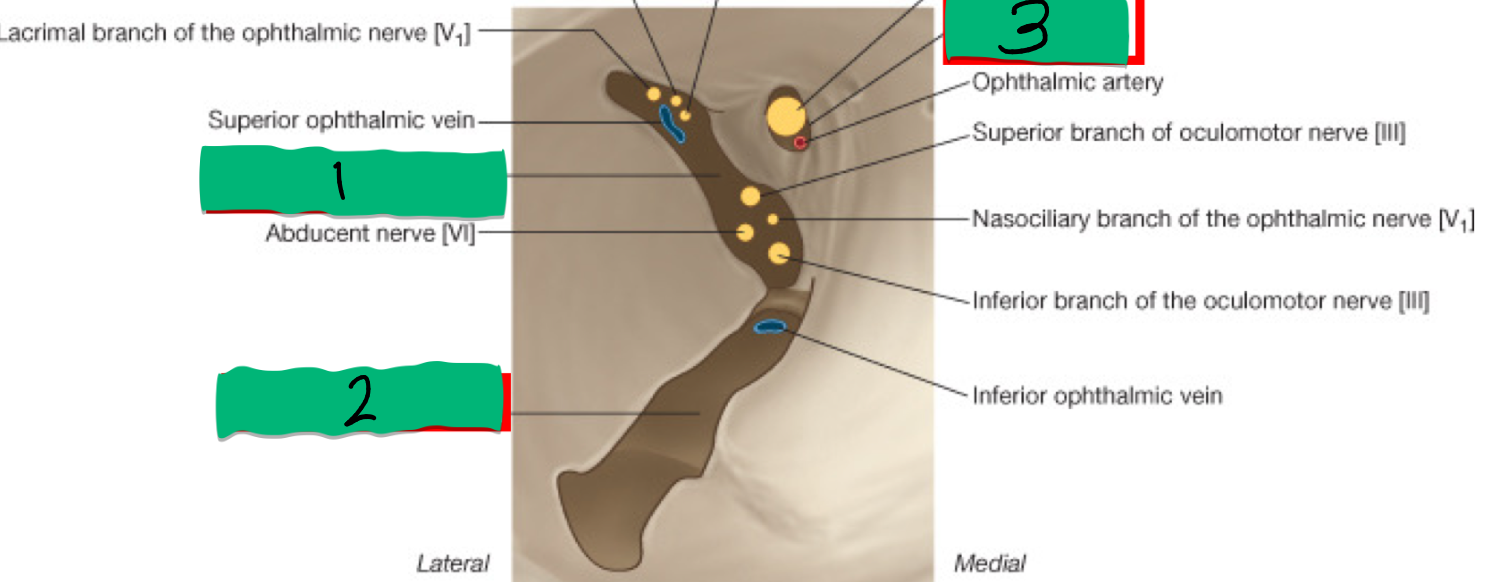

1

Optic Canal: CN II

2

Superior Orbital Fissure: CN III, IV, V1, VI

3

Foramen Rotundum: V2

What’s 1 and what nerve does it transmit?

Superior Orbital Fissure: transmits CN V1, CN III, IV, VI & Ophthalmic v

What’s 2 and what nerve does it transmit?

Inferior Orbital Fissure: transmits the Infraorbital nerve (CN V2)

What’s 3 and what nerve does it transmit?

Optic Canal: transmits Ophthalmic a. & CN II